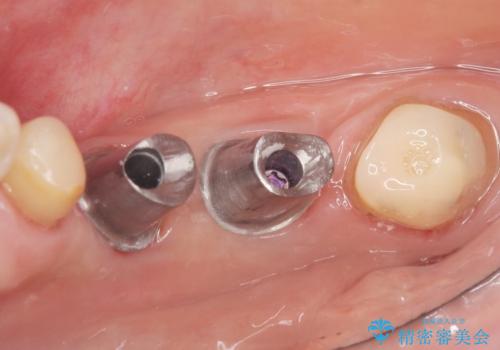

精査したところ、右下4の根尖病変及び右下5の欠損を認め、右下6は残根となり保存不可能な状態でした。

保存不可能な歯を抜去後、インプラント治療と根管治療を行いました。

- ¥1,177,000 (根管治療、土台、骨増生、インプラント・アバットメント×2本、仮歯・クラウン×3本) ※税込費用は治療当時の料金となります